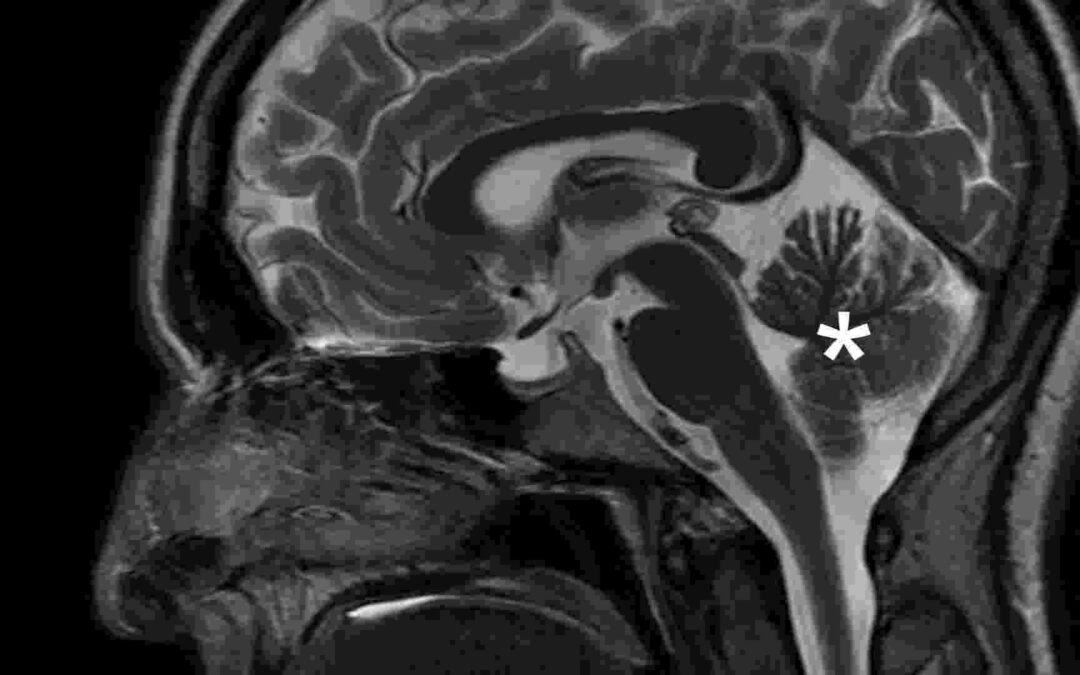

The Limbic System: An Overview Of Emotion And Healing

Ever wonder why a song can make you cry, or why a smell suddenly pulls up an old memory? The answer lies in a powerful part of your brain called the limbic system. This system acts like the emotional hub of your mind. It connects feelings, memory, and motivation into...